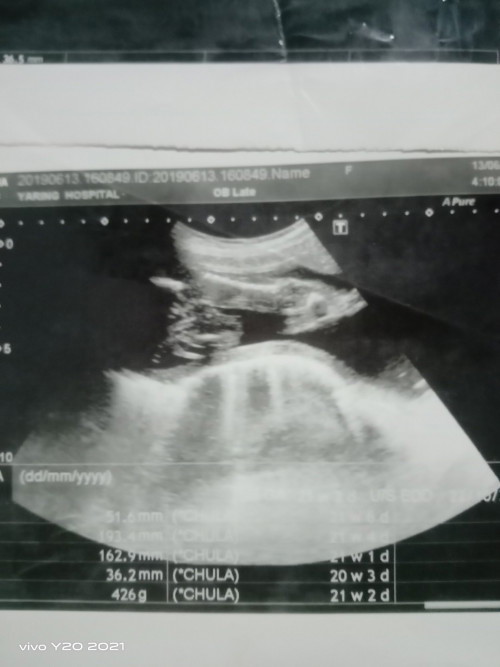

ไปซาวมาแล้วคุณหมอบอกน้องเป็นผู้หญิง แต่ทำไมเราเห็นตุ่มๆเหมือนไข่เลยคะ มีแม่ๆคนไหนได้รูปผลซาวประมานนี้แล้วเป็นผู้หญิงบ้างคะ แล้วผลซาวผู้ชายประมานไหนคะ 🤣